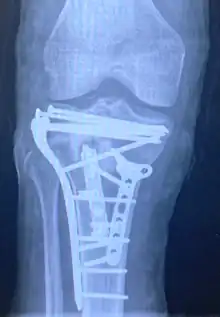

Repair of a tibial plateau fracture

Pain may be managed with NSAIDs, opioids, and splinting.[1][2] In those who are otherwise healthy, treatment is generally by surgery.[1] Occasionally, if the bones are well aligned and the ligaments of the knee are intact, people may be treated without surgery.[2] The surgery usually involves reducing the fractured fragments of the tibia plateau to their anatomical position and fixing them in place with screws only or fixed angle anatomical plates ensuring absolute stability. Implant selection is based on the type of injury. Generally, simple or incomplete fractures (Schatzker type 1) of the plateau are compressed with 6.5mm partially threaded cancellous screws. Complex type fractures will require a plate for enhanced stability. As the tibia condyles articulate with the femur (thigh bone) to form knee joint, any incongruity in the articular surface is unacceptable as it leads to early arthritis. Prolonged immobilization of the knee joint is also not recommended which result in stiffness of the joint and difficult recovery. It's currently debated what role primary total knee arthroplasty (Joint Prosthesis) plays in the treatment of tibial plateau fractures. Although accompanied with risks small studies have shown promising results.[9]